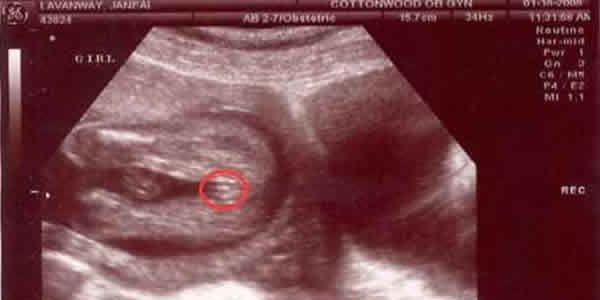

全能的大家都会想起很多怪异却又有点儿让人惊讶的念头。有传闻说,假如胎囊的长度宽的相距在一倍之上,那么男孩子概率大。长度宽相同,或是相距并不大得话,很可能是个女宝。那么事实是否那样的呢?

用B超精确测量胎囊,主要是用于估计孕龄,依据数据信息的转变,能立即发觉宝宝发育中的缺点。有母亲回望起当初怀孕时的B超数据信息,来认证了一下,例如有一位妈妈在怀孕8周时,胎囊是16毫米×17mm,結果生下了一位公主。因而由此可见,孕囊的大小并不能够表明胎宝宝的性别。